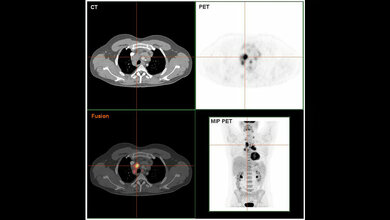

Die Wissenschaftler fanden in menschlichen Gehirnen eine ähnliche Situation vor. Bei Menschen mit primären oder sekundären Lymphomen im zentralen Nervensystem ist ebenfalls der NF-kappaB-Signalweg aktiviert und dadurch mehr CCL19 vorhanden. Der Botenstoff wird – genau wie bei den Mäusen – von speziellen Gehirnzellen, den Astrozyten ausgeschüttet. Damit liefern die DKFZ-Forscher nicht nur erstmals eine Erklärung dafür, wie sekundäre ZNS-Lymphome entstehen. „Wir haben entzündliche Gehirnveränderungen als potenziellen Risikofaktor für ZNS-Lymphome identifiziert“, sagt Heikenwälder.